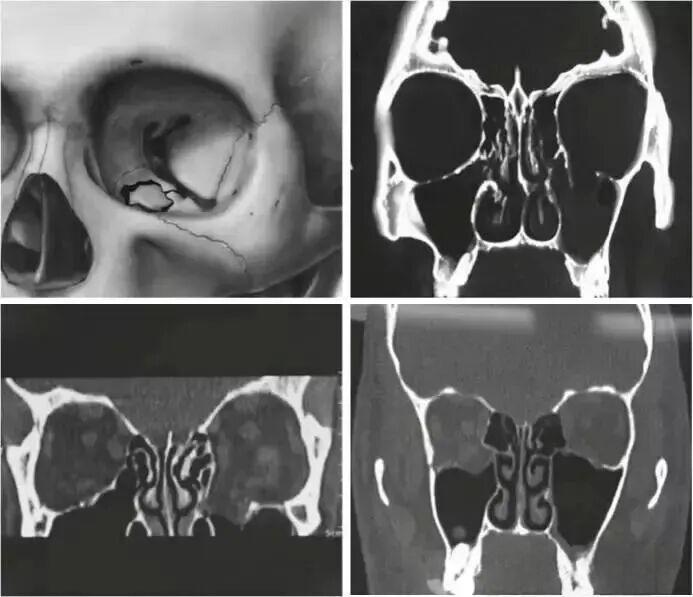

In recent years, the incidence of industrial injuries and traffic accidents has been on the rise, leading to an increasing number of patients with orbital fractures. The bone of the orbital wall is weak, and once a fracture occurs, it is highly prone to bone defects. In order to reconstruct the orbital structure, it is necessary to use biomaterials to replace the missing bone tissue. In the past, materials used for repairing eye sockets mainly included autogenous bone, hydroxyapatite, bioactive glass, and silicone gel. However, these materials all have varying degrees of defects and are prone to complications such as displacement and infection. In this context, in the early 1990s, titanium alloys began to be used for the repair of orbital wall fractures and defects, and quickly gained popularity due to their excellent properties.

Since its first successful application in orbital repair in 1990, Titanium Mesh has been widely used as a filling and internal fixation material for the repair of orbital wall and floor defects. However, it also has some issues that cannot be ignored.